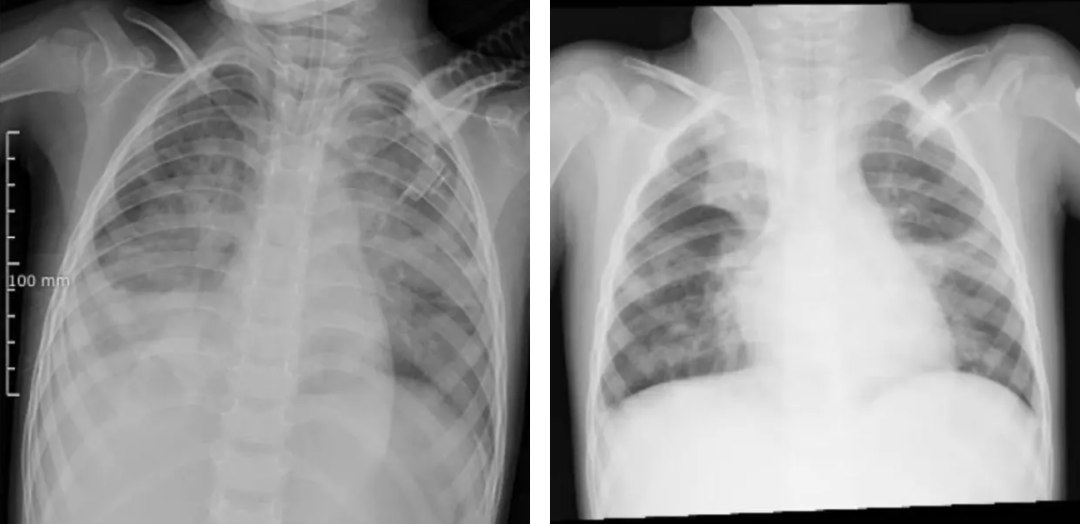

图源 河南省儿童医院(左图为ECMO上机前,肺部结构模糊,呈现“白肺”影像表现。右图为ECMO支持治疗5天后,肺部影像清晰度明显改善)

当地医院医疗团队几乎使用了所有常规治疗手段:有创呼吸机、高频振荡通气、一氧化氮吸入……然而,即使在极高的呼吸机参数支持下,朵朵的血氧饱和度仍仅能维持在80%-85%,呼吸衰竭难以纠正。

检查结果令人揪心:甲型流感病毒(H3N2)、金黄色葡萄球菌、流感嗜血杆菌,形成“病毒牵头、细菌跟攻”的“三重打击”,引发严重肺部感染,发展为急性呼吸窘迫综合征(ARDS),生命悬于一线。

让不少家长揪心

在常规治疗无效、命悬一线之际,河南省儿童医院ECMO团队携“人工肺”紧急跨市驰援,成功建立生命通道,完成了一场与时间赛跑的生死救援。上机一周后,经全面评估各项指标,朵朵顺利撤离ECMO,转入后续康复治疗阶段。